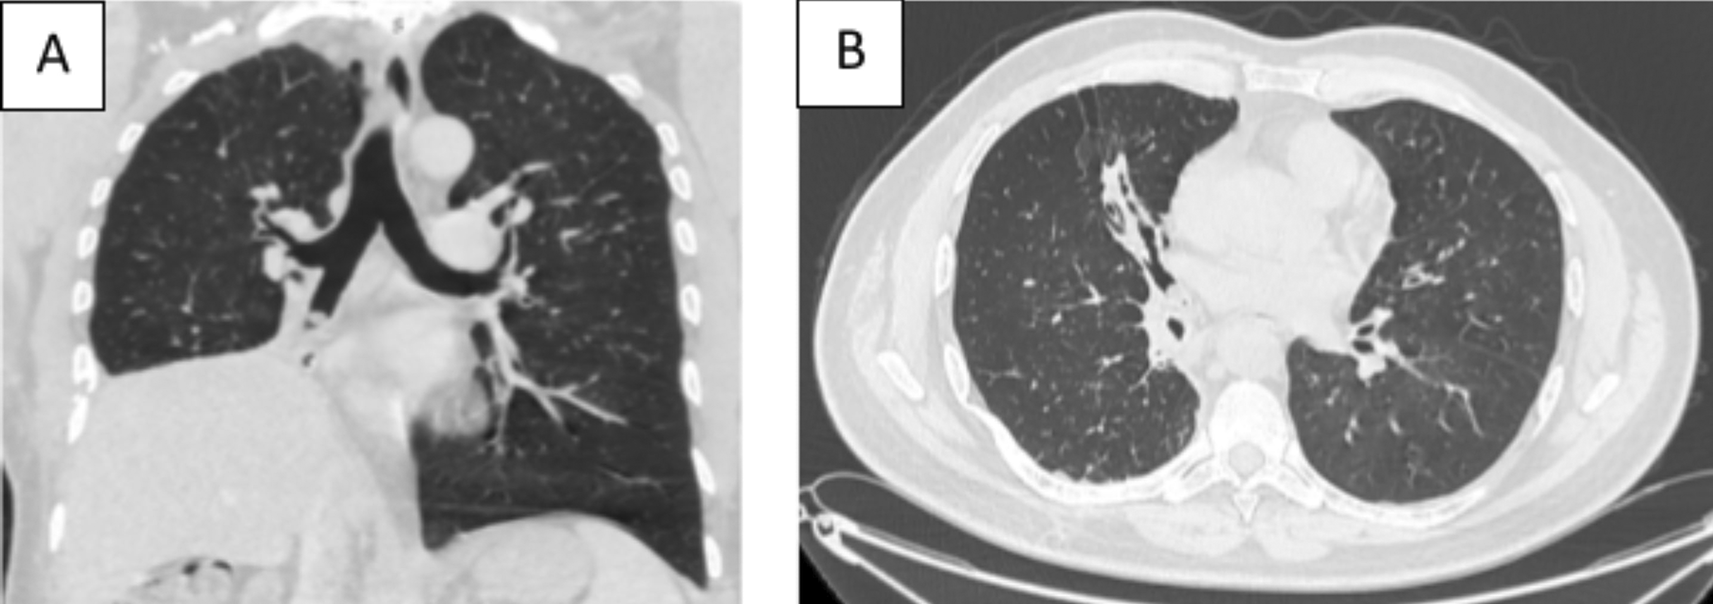

A 43-year-old nonsmoker man was referred to our department for respiratory preparation before surgical excision of an endobronchial HC. Medical history included sinonasal polyposis and diffuse bronchiectasis diagnosed at the age of 12 years with a negative etiological assessment and right lower lobectomy 4 years ago. On admission, the patient had purulent sputum with no other associated symptoms, including fever, dyspnea, or hemoptysis. Chest auscultation revealed wheezing, and the patient’s oxygen saturation level was 93% (room air). The patient was treated for a bronchial superinfection. Results of microbiological investigations were negative. Flexible bronchoscopy performed after the patient improved revealed a yellowish polylobed budding formation that completely obstructed the middle lobe bronchus (Figure 7). Chest CT-scan revealed an endobronchial lesion of fatty density in the middle lobe bronchus measuring 13 mm, responsible for minimal bronchiectasis of the middle lobe downstream, with almost total atelectasis of the latter, minimal bronchiectasis of the superior lingular segment, and sequelae of right lower lobectomy (Figure 8). After a multidisciplinary discussion and consideration of the patient’s history, endoscopic treatment was decided. Rigid bronchoscopy revealed a smooth pale pink tumor that completely occluded the middle lobe bronchus and protruded into the bronchus intermedius (Figure 9). Diode laser treatment (20 W, 620 J) was performed before mechanical ablation of the tumor using the tip of the bronchoscope. No additional instruments were required. After removal, total recanalization of the middle lobe bronchus and its subsegments without endobronchial secretions was observed. Macroscopic examination revealed 2 fragments measuring 1.5 * 1.5 cm and 0.5 cm long axis, yellowish in color and with a smooth surface (Figure 10). No complications such as bleeding, respiratory failure, or superinfection occurred. Histopathological examination of the samples stained with Hematoxylin and Eosin (H&E) showed the presence of nodules of hyaline cartilage admixed with fibrous adipose tissue, spindle cells, and myxoid stroma (Figure 11). The diagnosis of endobronchial HC was confirmed. Flexible bronchoscopy performed 2 months after patient discharge revealed recurrence of a small yellowish formation, which reduced the lumen by 50% and was completely resected with biopsy forceps. Histological examination revealed an ulcerated bronchial mucosa seat of a hyperplastic fleshy bud, without signs of specificity or malignancy. No recurrence was observed after a follow-up period of 12 months.